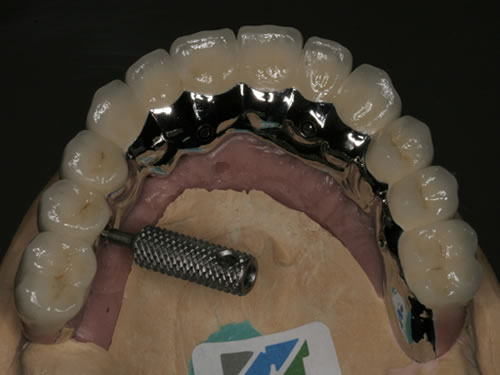

Für den zahnlosen Ober- und Unterkiefer werden dies häufiger Stegkonstruktionen oder Teleskopversorgungen sein (Abb. 8.8 bis 8.16).

Abb. 8.10: Individueller Stahlsteg auf 4 Implantaten im zahnlosen Oberkiefer.

Abb. 8.12: Zahnloser Oberkiefer mit 8 Implantaten und eingesetzter Unterkonstruktionen.

Auch eine festsitzende zementierte oder verschraubte Brücke ist möglich (Abb. 8.17 bis 8.19). Hierbei muss eine günstige Lachlinie vorliegen und der Kieferschwund sollte noch nicht zu weit fortgeschritten sein. Die Zähne würden sonst sehr lang wirken, da die Zahnpositionen in die ehemalige Position der Zähne zurückgebracht werden muss. Langes Prothesentragen und entsprechender Knochenverlust erschweren besonders im Oberkiefer festsitzenden Zahnersatz. Sehr exakte Voruntersuchungen und präzise Implantatpositionen mit entsprechenden Knochenaufbaumaßnahmen sind häufig notwendig, um den Patienten diesen Wunsch zu erfüllen.

Abb. 8.17: Verschraubte Brücke auf Implantaten im zahnlosen Oberkiefer (Modellansicht).